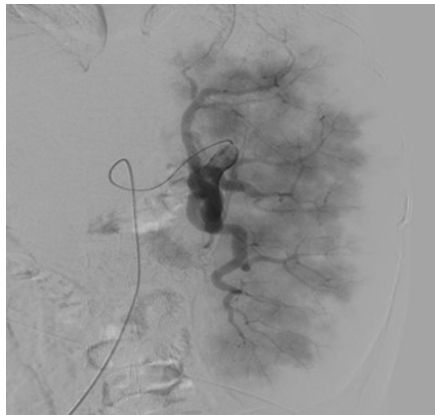

本刊推荐:为探讨脾动脉栓塞术(SAE)在Caroli综合征(CS)合并门静脉高压伴脾功能亢进患者中的治疗价值,研究人员开展病例研究。结果显示SAE可显著提升血小板计数(从29,000/μL升至394,000/μL),但术后出现发热、白细胞升高(WBC 19,000/μL)等栓塞后综合征。该研究为晚期Caroli综合征的并发症治疗提供了新思路,强调早期肝移植的重要性。